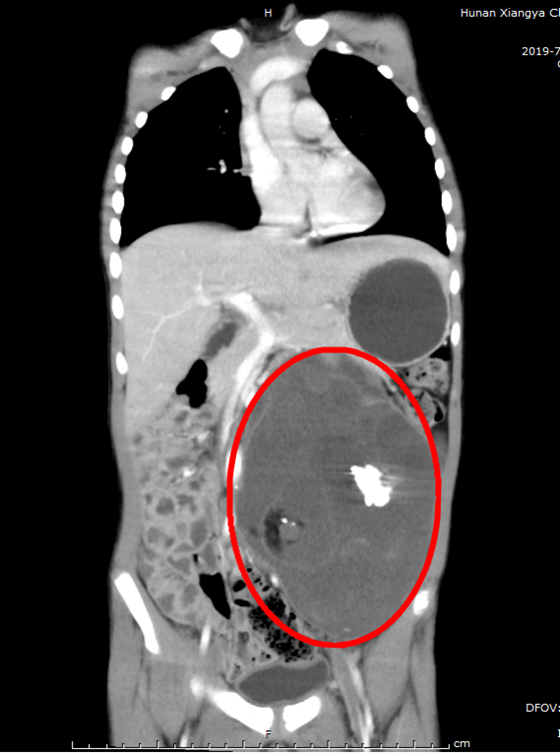

经普外科完善增强CT、肿瘤周围血管成像CTA/CTV等检查后,发现小诚的腹中肿瘤约12厘米*10厘米的肿瘤,考虑为腹膜后畸胎瘤,肿瘤压迫了左侧输尿管引起了左肾积水并将腹主动脉向右明显推压。如果放任肿瘤长大可能会导致左肾萎缩失去功能,并可能压迫周围血管造成静脉血栓、肠坏死等严重后果。湘雅常德普外专家对小诚的情况做了充分详细讨论,并制定了相应手术方案。